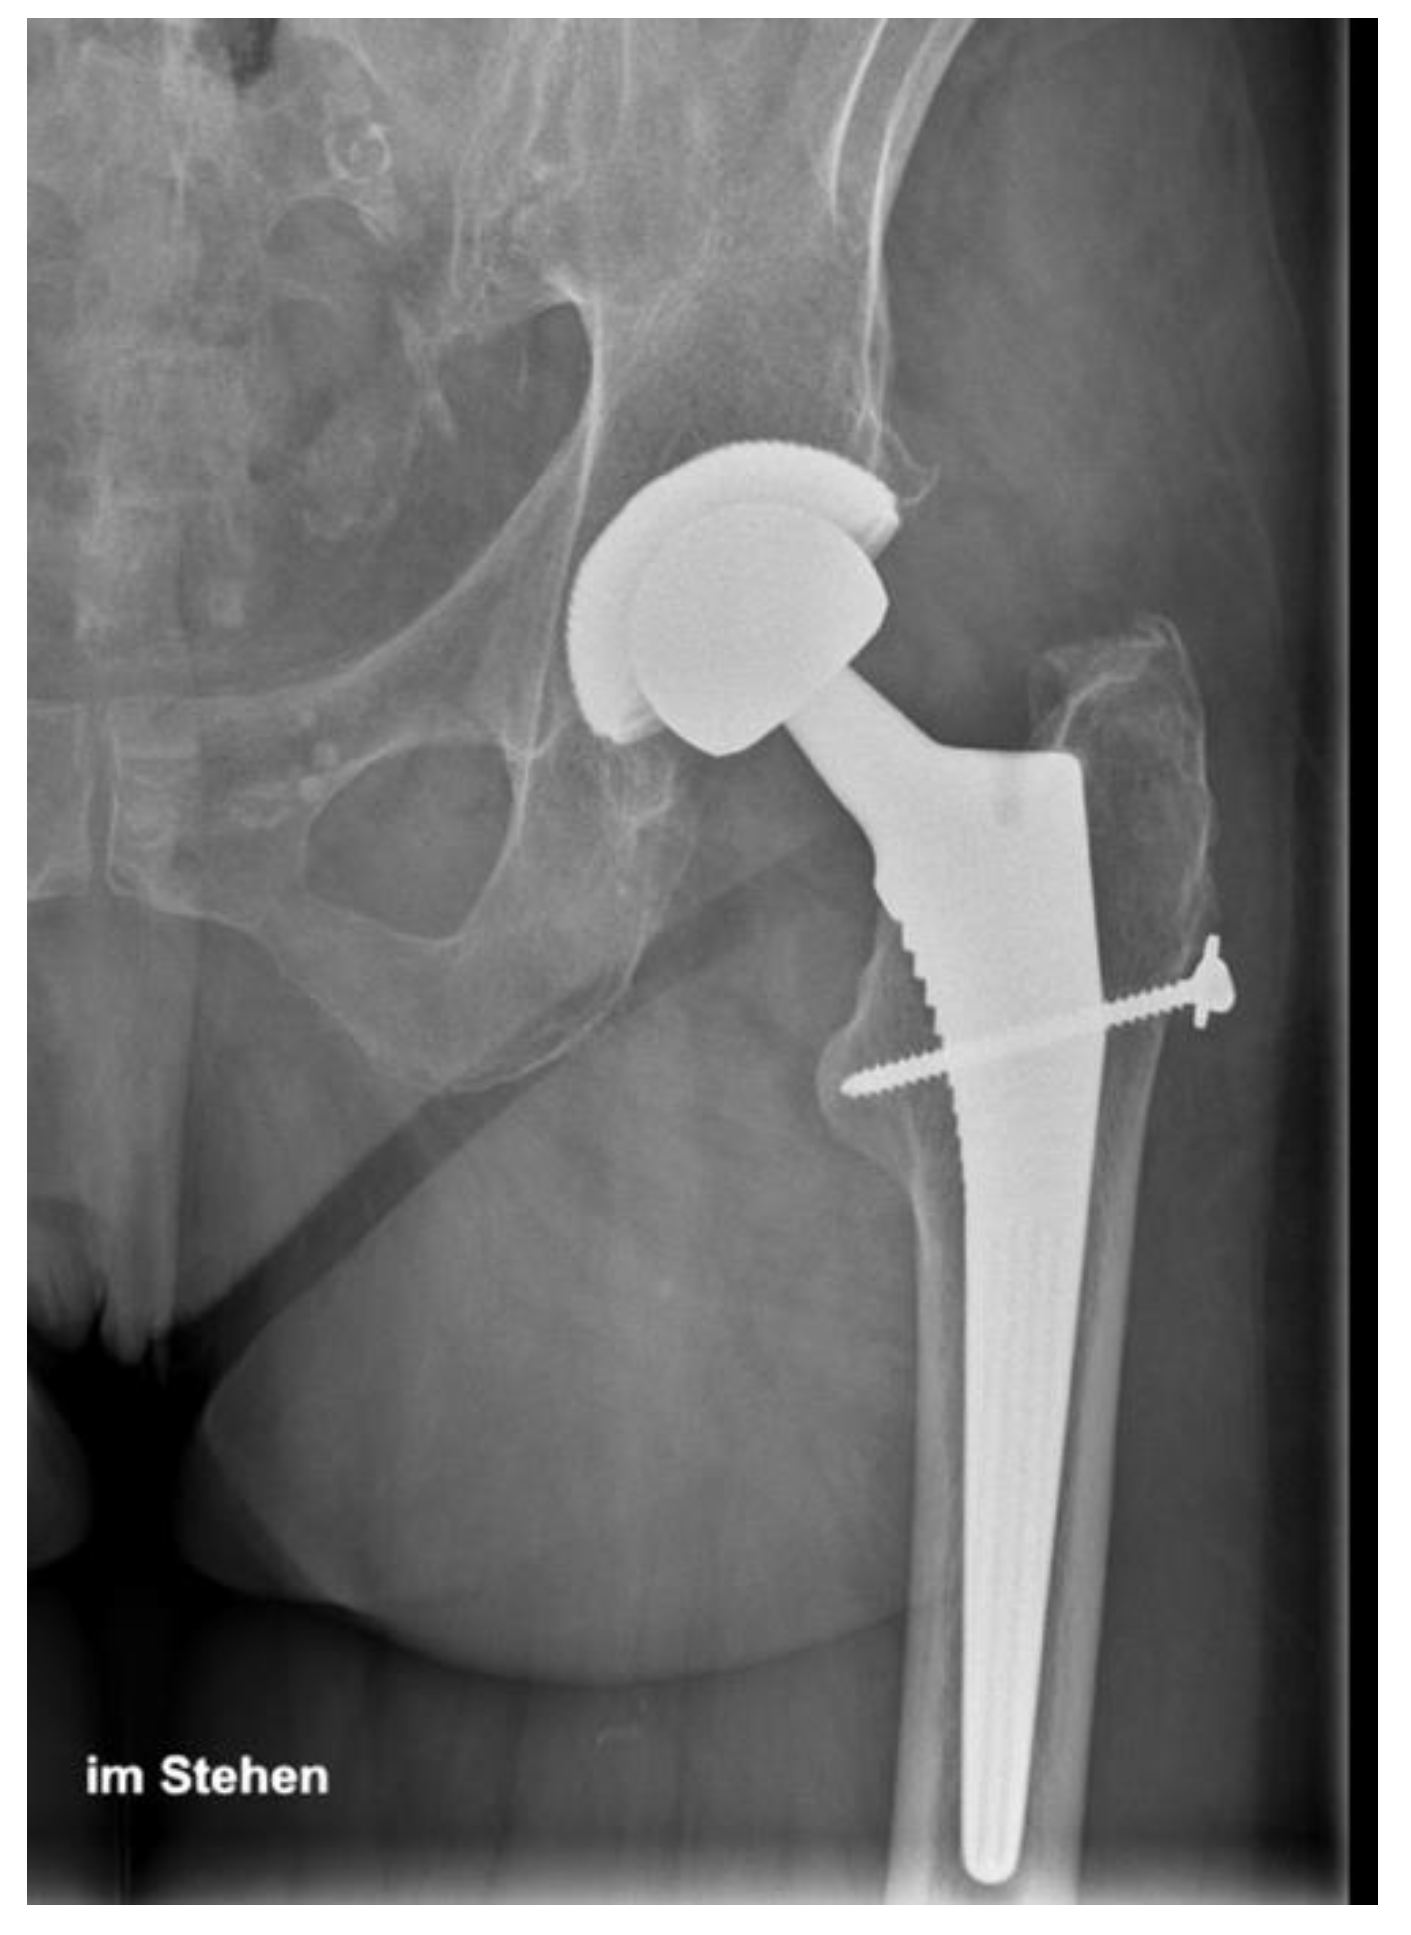

3.3. Radiographic Results